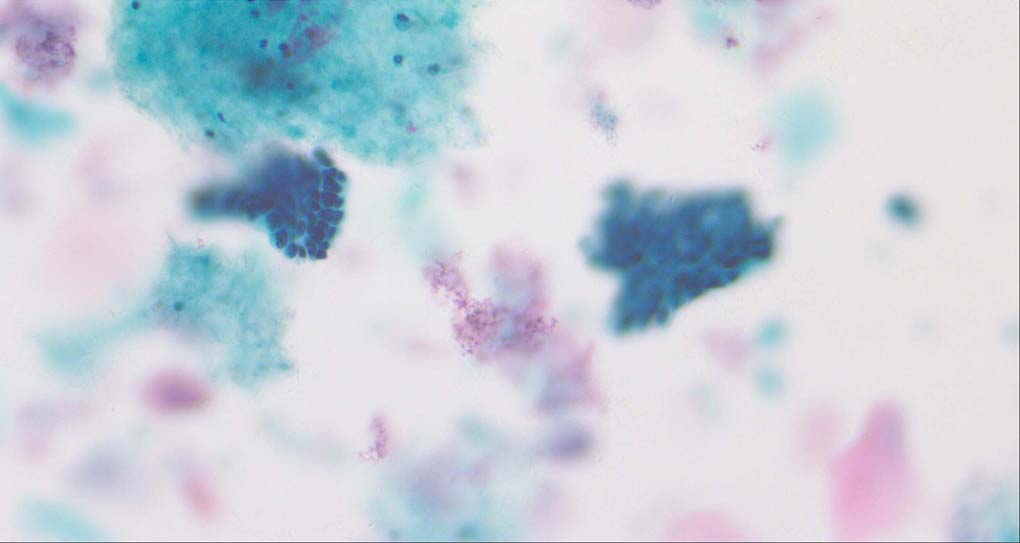

Pixel-level image fusion intends to combine different images of the same scene by mathematical techniques in order to create a single composite image that will be more comprehensive and thus, more useful for human or machine perception [1, 2]. For instance, multi-modal image fusion [3] tries to fuse images which have been acquired via different sensor modalities exhibiting diverse characteristics for a more reliable and accurate medical diagnosis. Another typical application is the multi-focus image fusion [4]. As the depth-of-field (DoF) of bright-field microscopy is only about 1~2 micrometers, while the specimen’s profile covers a much larger range and then the parts of the specimen that lie outside the object plane are blurred. The multi-focus image fusion can obtain an all-in-focus image from multiple images taken under different distance from the object to the lens of the identical view point.

A good image fusion method should contain the following properties. First, it preserves both the details of small size objects and the integrity information of large size objects in the fused image, even in the case of the size of the interested objects varying largely in the image. For example, the cervical cell images from the microscope contain both small size isolated cells and large size agglomerates, which are both useful for cervical cytology [5]. Second, it should be efficient enough to handle large-scale data. For instance, it needs to process thousands of fields of view (FoV) in an acceptable time for the whole slide scanning in digital cytopathology [6], which requires to fuse a series of high resolution images captured at each FoV in a very efficient way. Third, it does not produce obvious artifacts. Despite being studied extensively, to our best knowledge, existing fusion methods may not meet these requirements simultaneously.

To demonstrate the effectiveness and efficiency of the proposed image fusion method , we conduct a set of comparative experiments on three image datasets. The first is composed by 8 pairs of multi-modal medical images and the second one contains 15 pairs of multi-focus gray or color natural images. These two datasets are often used in many related papers and some examples are shown in Figure 3(a) and Figure 3(b). The third one is a new multi-focus cervical cell image dataset collected by ourselves, which consists of 15 groups of color images and each group contains a series of multi-focus cervix cell images with size of or , etc. Some source examples are shown in Figure 3(c). Our source code implemented in C++ along with the new multi-focus cervical cell image dataset is available online.

Figure 9, Figure 10 and Figure 11 show the comparative fused results of the multi-focus cell images shown in Figure 3(c). For clarity, we also present a closeup view in the right-bottom of each sub-picture in Figure 9 and Figure 10. As shown in the close-up views of Figure 9, the fused images based on DSIFT, IM, MWGF and BF methods are extremely blurred in the boundary and fail to keep the details of cell nucleus. Furthermore, the DTCWT and NSCT based methods produce halo artifacts in the fused images, while GFF and CNN based methods fail to preserve the small cell nucleus. LP-SR based method nearly works fine which keeps the most of the details of the small size cells, but the integrity of the clustered large size cells is damaged. Fortunately, in our proposed method, the integrity of the clustered large size cells is preserved and most of the isolated small size cells are maintained from the original images, which demonstrates the best visual quality.

Similarly, as shown in the close-up views of Figure 10, the fused images from DSIFT, IM, MWGF and BF are blurred and lose some nucleus details, while the results from DTCWT, GFF, CNN and NSCT produce halo artifacts. LP-SR based method can keep details well but also produces halo artifacts and other noise. Our method can preserve the focused areas of different source images well without introducing any artifacts. For the example illustrated in Figure 11, the fused images generated by DSIFT, DTCWT, IM and NSCT all fail to preserve the focused areas of different source images and result in extremely blurred images. The GFF, CNN, MWGF and BF based method introduces a lot of color distortion of the nucleus regions and the obvious halo artifact. The result of LP-SR based method is close to the one of our method but introduces some odd color distortion. Again, our method produces fused image which can preserve the focused areas of different source images well without introducing any artifacts.